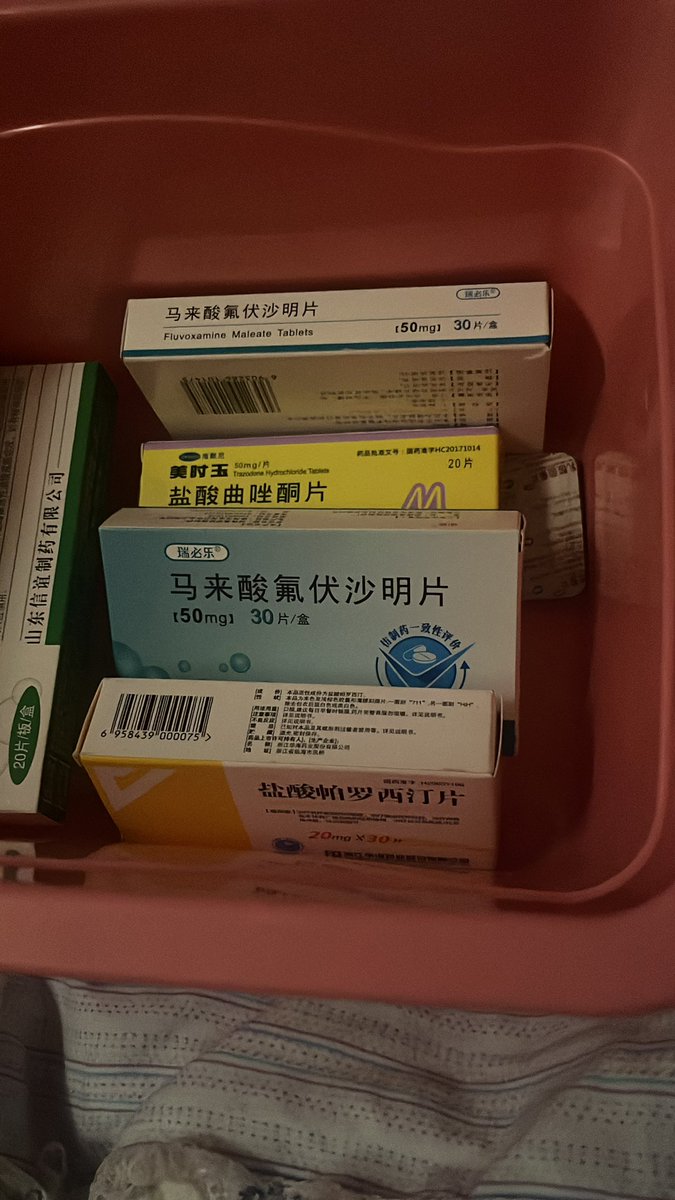

对于药物过量引起的中枢神经系统副作用,有一些不常见或常见的药物来控制症状。

罗通定:拮抗多巴胺

赛庚啶:血清素综合症

异丙嗪:在低剂量下没有抗精神病作用,和其他所有抗组胺药一样可以缓解过敏。止吐

喹硫平:不清楚是什么引起的症状就干脆谁都别玩了吧()似乎很万能的急救

评论区欢迎补充 https://t.co/7S4tGVDEM5